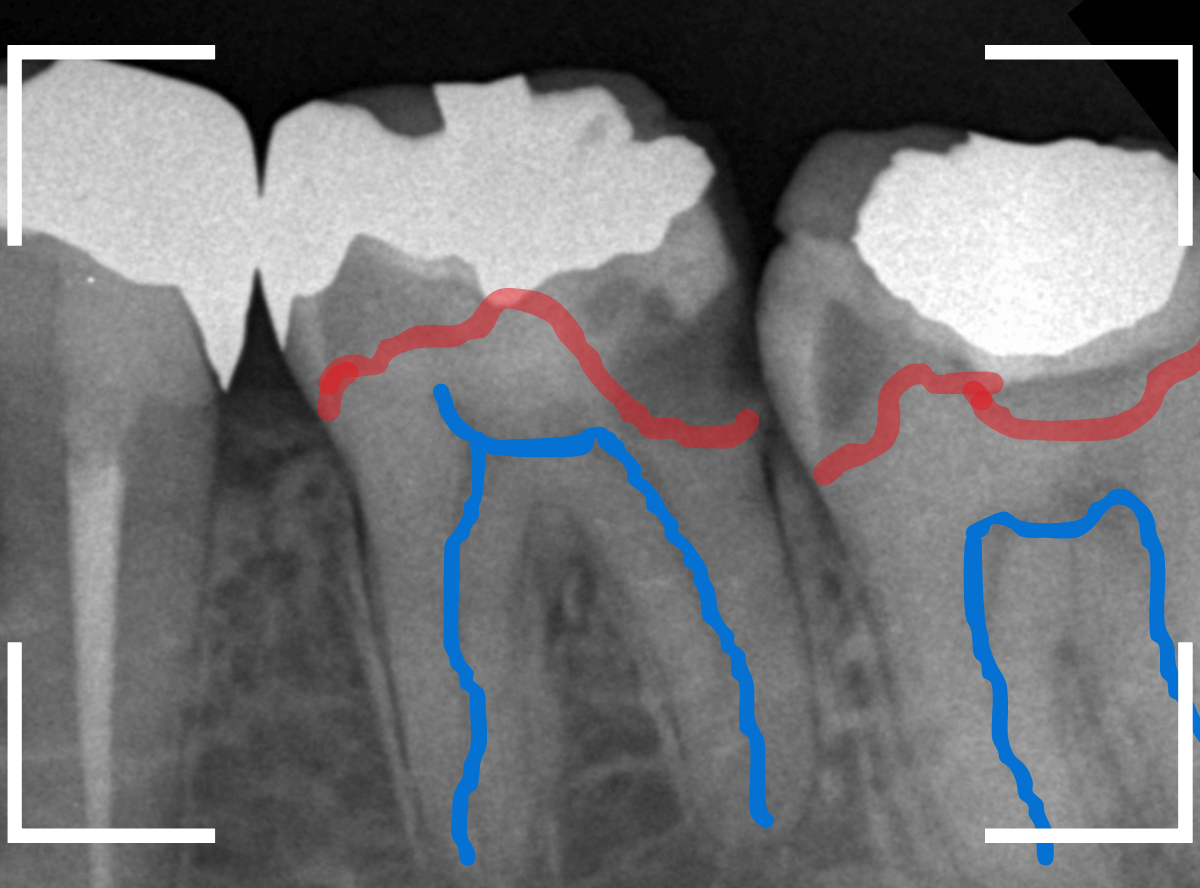

Case.14 インレーの下の歯肉まで広がった虫歯

「下の奥歯が噛むと痛む」という症状で来院された患者さんのケースです。

お口の中の状態を確認すると、奥歯の端に穴が開いているのが見えます。

ここかな?

レントゲン写真で確認します。

やはり、奥歯の端が大きな虫歯になっています。

青いラインが歯の神経、赤いラインが虫歯です。

レントゲン写真上では虫歯が神経まで達しているように見えます。

これは、神経を取らないとダメかもしれません。